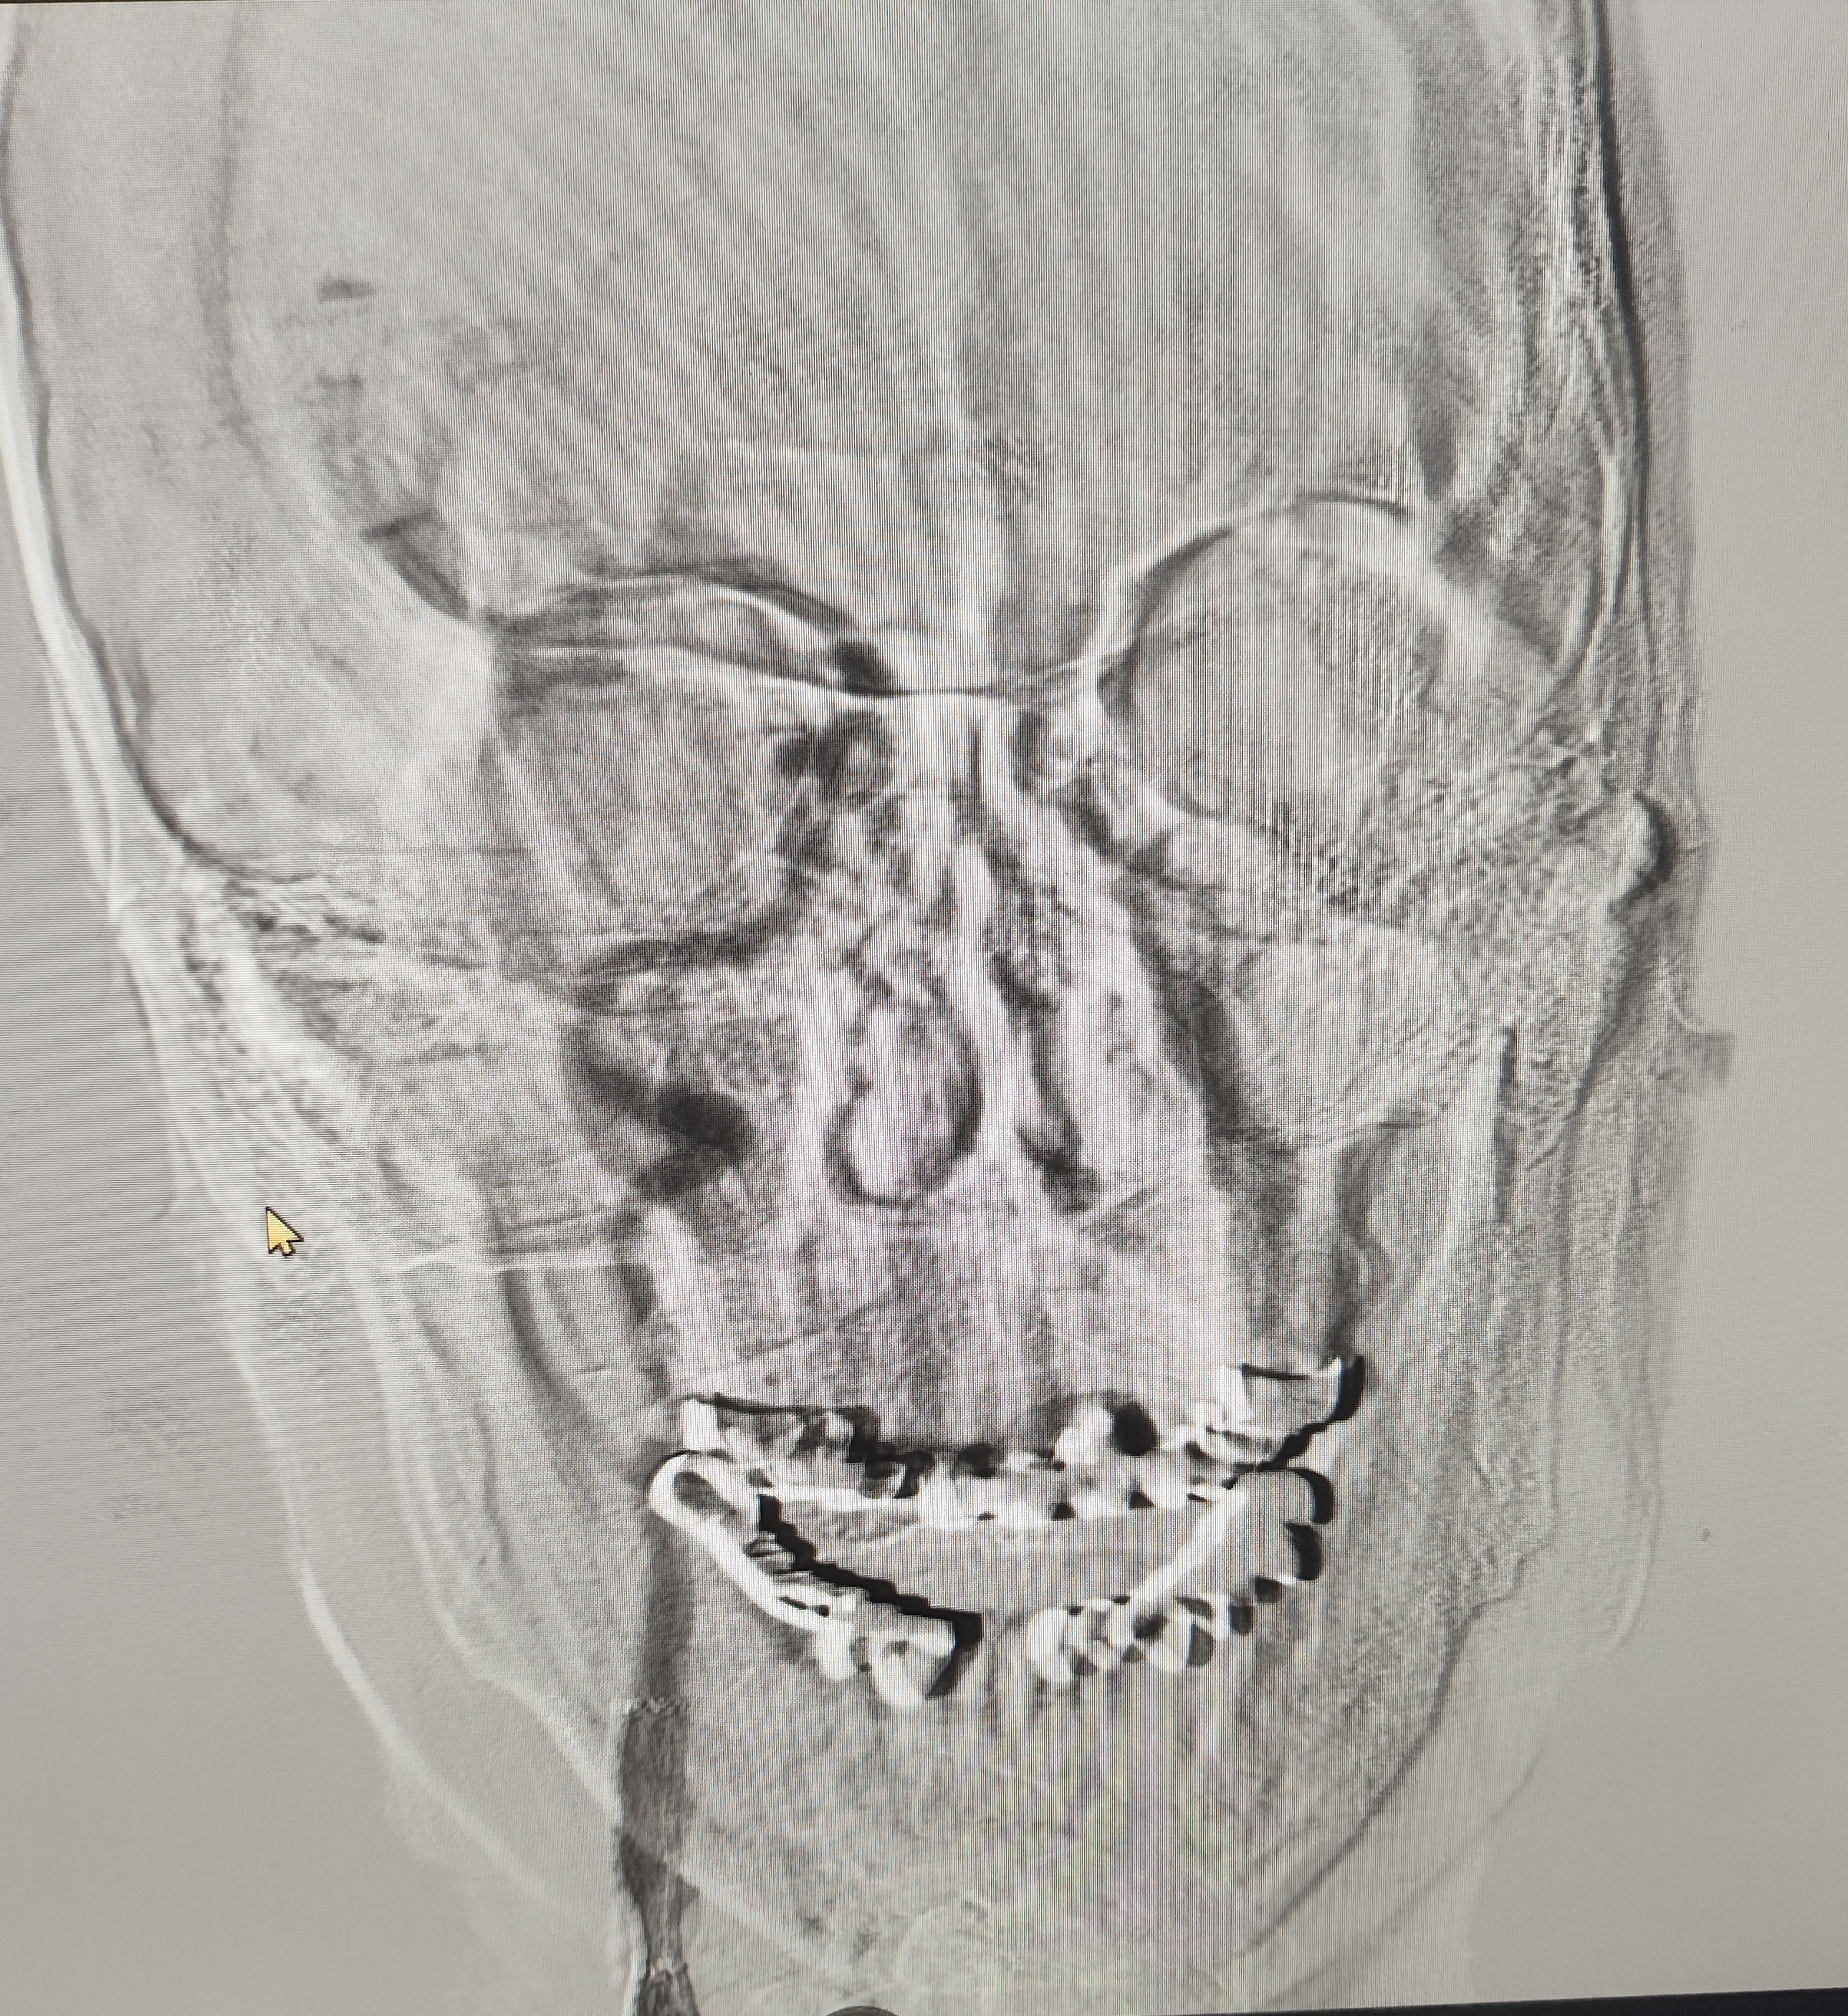

颈总巨大斑块急性闭塞的血管内治疗(双颈动脉支架桥接+支架释放后掉斑块,抽吸取栓)

84岁男性,既往右侧颈动脉狭窄病史8个月,多次脑梗未治疗,本次突发左侧肢体无力来诊,发病30小时后转入我院。

急诊上台。